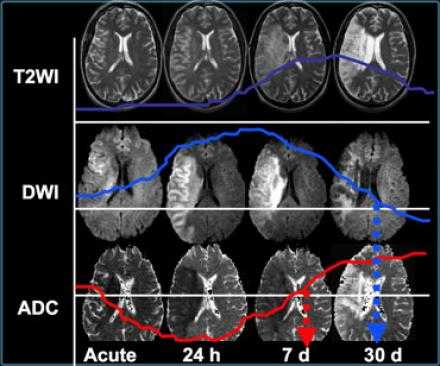

Когда мы сравниваем результаты на T2WI и DWI во времени, мы заметим следующее: В острой фазе T2WI норма, но со временем зона инфаркта станет гиперинтенсивной. Гиперинтенсивность на T2WI достигает своего максимума между 7 и 30 дней. После этого сигнал начинает угасать. На DWI гиперинтенсивная область в острой фазе, а затем становится более интенсивной с максимумом на 7 дней. На DWI у пациента с инфарктом головного мозга визуализируется гиперинтенсивная область примерно на 3 недели после начала заболевания (при инфаркте спинного мозга на DWI визуализируется гиперинтенсивная область на одну неделю!). На ADC будет сигнал низкой интенсивности с минимальной интенсивностью в первые 24 часа, после сигнал будет увеличиваться в интенсивности и, наконец, становится максимально интенсивным в хроническую стадию.

Псевдо-улучшение на DWI.

Псевдо-улучшение наблюдается на 10-15 день. Слева показана норма на DWI. На T2WI там могут быть гиперинтенсивная область в правой затылочной доле в сосудистой территории задней мозговой артерии. В T1WI после введения контрастного препарата на основе гадолиния визуализируется повышение сигнала (зона инфаркта указана стрелкой).

Прежде считалось, что гиперинтенсивный сигнал на DWI — это мертвые ткани. Новейшие исследования доказывают, что некоторые очаги из них вероятно могут быть потенциально обратимым повреждениям. Это наглядно показано, если сравнить изображения одного и того же пациента DWI в острейшую фазу и Т2WI в хроническую фазу. Размер поражения на DWI намного больше.